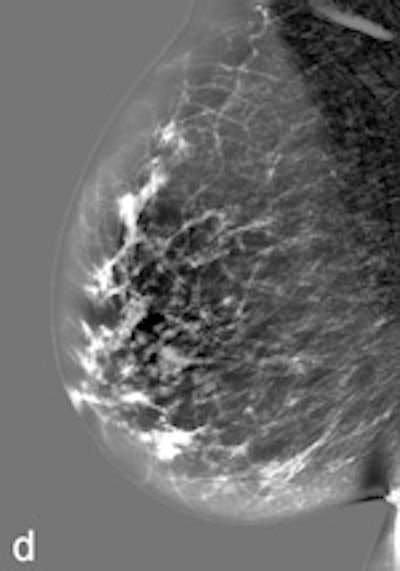

| Example of a subtle finding in a right-sided mediolateral oblique view, which was only reported by radiologists when using premium view (PV). A: Digitized prior. B: Tissue equalization (TE) processed image. C: PV processed image with the annotation. D: The resulting image of subtracting TE from PV. E: Thresholded version of D. White areas indicate that pixels in the PV image have relatively higher intensity than the related pixels in the TE image, whereas black areas indicate the opposite. In PV images, low-frequency trends are suppressed (no noticeable signal decrease in the breast edge in PV compared with TE), whereas higher-frequency structures are emphasized (e.g., glandular structures). All images courtesy of Wouter Veldkamp, PhD, Leiden University Medical Center. |

The cases were acquired using the Senographe Essential digital mammography system (GE Healthcare). Tissue equalization is a standard GE application that corrects for low-frequency variations resulting from under- and overpenetration of x-rays. As a result, the image dynamic range is reduced, enabling improved soft-copy image display.

The local contrast optimization, premium view, has been designed to improve the quality of the information presented to the radiologist for diagnosis and also the reading speed by optimizing the local contrast in breast structures. In premium view, low-frequency structures are obtained from the original image by low-pass filtering. High-frequency structures are obtained by subtracting the low-pass filtered image from the original image. The low- and high-frequency images are both processed and weighted individually, then added together. The resulting image exhibits reduced contrast between different tissue types but enhanced contrast of small-scale anatomical architecture.

Another example of a finding in a left-sided craniocaudal view that was reported clearly more often by radiologists when using premium view (PV). A: Tissue equalization (TE) processed image. B: PV processed image with the annotation. C: Similar to image above, the resulting image of subtracting TE from PV. D: The thresholded version of C.For all six radiologists, perceived case suspiciousness -- defined as the highest probability of malignancy of all radiologist findings -- was higher using premium view optimization.

The major difference between the processing algorithms was an additional local contrast optimization when premium view was applied. "Premium view is aimed at increasing the visibility and suspiciousness of malignant lesions, but in our study the perceived suspiciousness of benign lesions and normal cases is increased as well," the researchers wrote. "An effect of local contrast enhancement could be that both normal (dense) structures and abnormal structures appear more suspicious due to their enhanced signal."